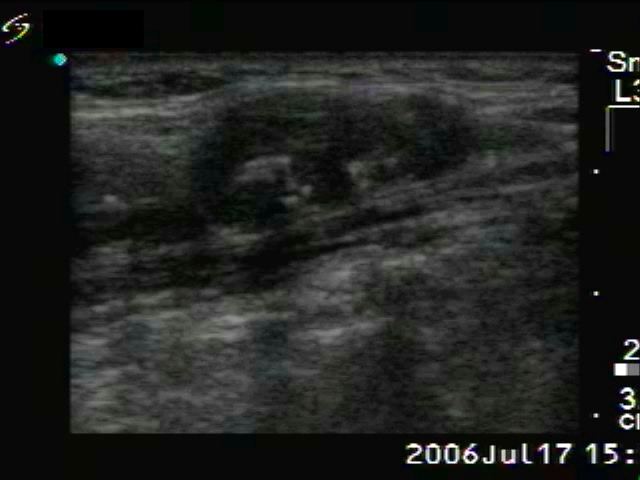

Medullary carcinoma (histological diagnosis) - case 638

There is an irregular minimally hypoechogenic-echonormal small patch in the central part of the hypoechogenic nodule. This figure has one bright granule in the left image.